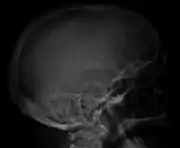

The diagnostic examination of a person with suspected multiple myeloma typically includes a skeletal survey. This is a series of X-rays of the skull, axial skeleton, and proximal long bones. Myeloma activity sometimes appears as "lytic lesions" (with local disappearance of normal bone due to resorption) or as "punched-out lesions" on the skull X-ray ("raindrop skull"). Lesions may also be sclerotic, which is seen as radiodense.[70] Overall, the radiodensity of myeloma is between −30 and 120 Hounsfield units (HU).[71] Magnetic resonance imaging is more sensitive than simple X-rays in the detection of lytic lesions, and may supersede a skeletal survey, especially when vertebral disease is suspected. Occasionally, a CT scan is performed to measure the size of soft-tissue plasmacytomas. Nuclear Medicine Bone scans are typically not of any additional value in the workup of people with myeloma (no new bone formation; lytic lesions not well visualized on nuclear bone scan).

Skull X-ray showing multiple lucencies due to multiple myeloma

Bone pain

Bone pain affects almost 70% of people with multiple myeloma and is one of the most common symptoms.[2]: 653 [22] Myeloma bone pain usually involves the spine and ribs, and worsens with activity. Persistent, localized pain may indicate a pathological bone fracture. Involvement of the vertebrae may lead to spinal cord compression or kyphosis. Myeloma bone disease is due to the overexpression of receptor activator for nuclear factor κ B ligand (RANKL) by bone marrow stroma. RANKL activates osteoclasts, which resorb bone. The resultant bone lesions are lytic (cause breakdown) in nature, and are best seen in plain radiographs, which may show "punched-out" resorptive lesions (including the "raindrop" appearance of the skull on radiography). The breakdown of bone also leads to the release of calcium ions into the blood, leading to hypercalcemia and its associated symptoms.[23]